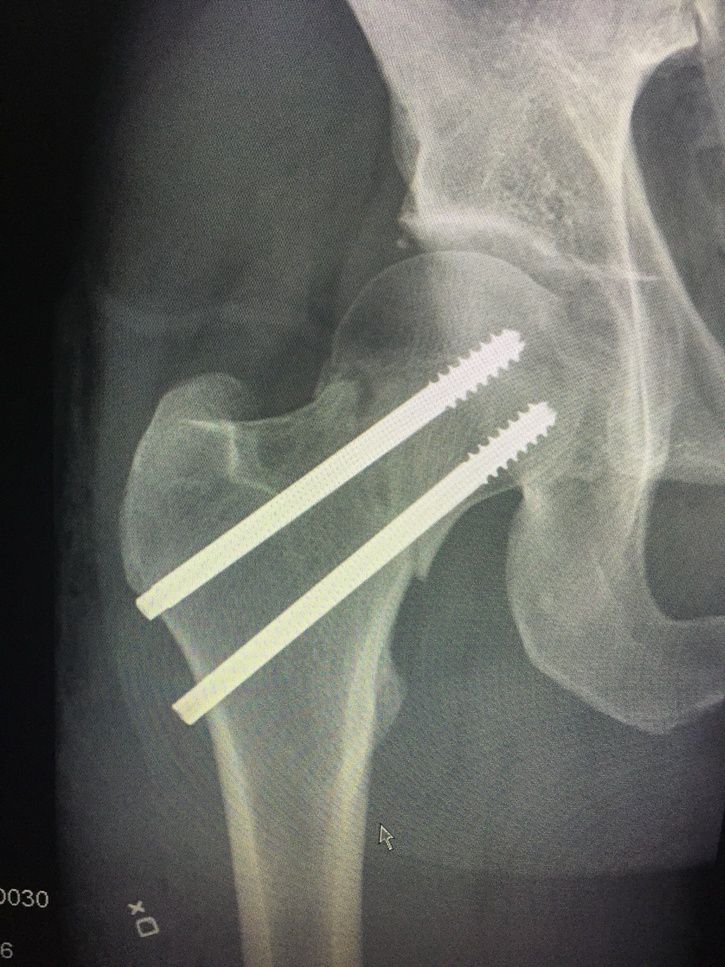

Det var jag som lyckades bryta lårbenshalsen. Det var flera som erbjöd sig stanna och hjälpa till men jag ringde som sagt själv till sjukvård. Var min första ESS men förhoppningsvis inte min sista(lite oviss framtid nu). Var sjukt kul cykling även om den var på gränsen till för svår för mig =)

Stort tack till fantastiskt agerande av sjukvård- och Gesunda-personal!

Nu väntar 6 månaders rehab.